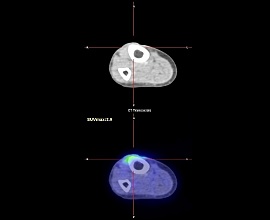

悪性結節性汗腺腫

20年前右下腿を裂傷、他院にて縫合手術施行。10年前より同部位にしこりを自覚し徐々に増大し色調変化及び硬結を認めた。腫瘍を疑い局所麻酔下にて切除を施行した。

病理診断結果は、エクリン汗腺由来の悪性結節性汗腺腫であった。

PET-CT画像